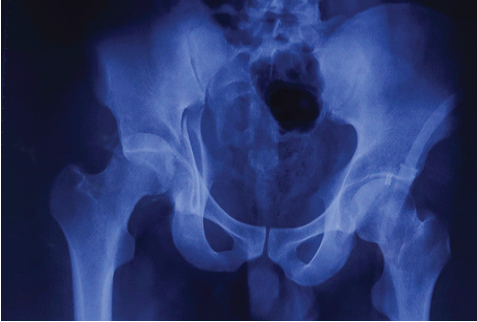

A 26-year-old male presented after a high-velocity road traffic accident with isolated left hip trauma. He was hemodynamically stable with no associated head, thoracoabdominal, or spinal injuries. The left lower limb appeared shortened and internally rotated, with severe hip pain and restricted active and passive motion. Distal pulses were palpable, and sensory and motor examination of the sciatic and femoral nerve distributions was normal. Anteroposterior pelvic radiographs (Fig. 1) and Judet views showed disruption of both the iliopectineal and ilioischial lines, indicating involvement of the anterior and posterior columns, with preservation of the obturator foramen, consistent with a both-column pattern. Computed tomography (CT) with three-dimensional reconstruction confirmed an anterior column posterior hemi-transverse acetabular fracture involving the weight-bearing dome and posterior wall (Fig. 2) according to the Letournel classification.

Figure 1: Anteroposterior radiograph of the pelvis at presentation showing disruption of the iliopectineal and ilioischial lines consistent with a both-column acetabular fracture, with the femur head subluxation.